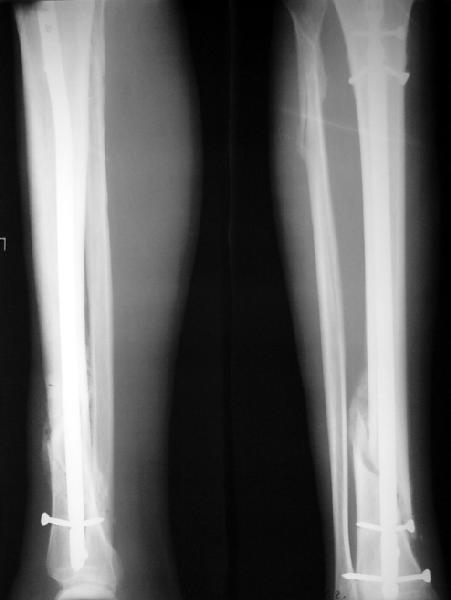

На мой взгляд, на снимках, приведённых Вами - неправильно сростающийся перелом дистальной трети большеберцовой кости, состояние после остеосинтеза интрамедуллярным гвоздём.

Как Вы пишите снимок под номером 1 - менсяц после операции, под номером 2- два месяца после операции.

Установка с медиальной стороны гвоздя в области дистального фрагмента дополнительного шурупа помогло бы Вам репонировать и удержать перелом в анатомическом положении, предотвратило варусную деформацию и смещение по ширине.

I think that the X-Rays show S/P IMN of Spiral # of the Distal Tibia consoles in misalignment.

Let to express concerning technique of operation my opinion... Insertion of a screw to medial side of a nail in distal fragment would help you to reduction and to keep this fracture in anatomic position has prevented varus deformity and displacement on width. By the way, if it is possible send a postoperative picture.